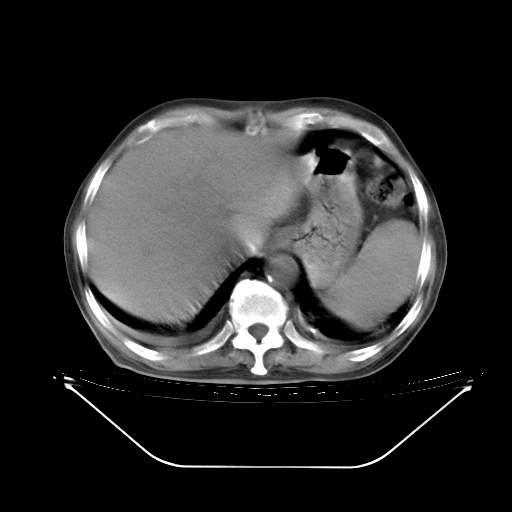

今天复查肺部CT,发现双肺广泛磨玻璃样改变。所以我把3月19日和5月9日相隔50天的肺部CT上传。请大家会诊。

5月9日肺部CT(在4月27日齐鲁医院肺部CT描述部分肺组织磨玻璃样改变,12天后肺组织广泛磨玻璃样改变)

2009年5月9日肺部CT